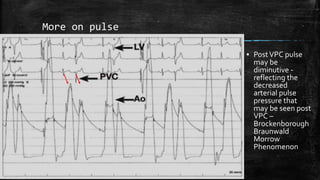

More on Pulse ▪The classic pulse contour in HC consists of a rapid upstroke, followed by a midsystolic dip or collapse, ▪ Which in turn is followed by a second late systolic wave ▪ The first peak is the equivalent of a sharp percussion wave, and the second peak represents a prominent, delayed tidal wave ▪ The mechanism for the secondary wave is unclear; the second peak occurs at the time when LV ejection is minimal, and it probably is a reflected wave or rebound phenomenon ▪ The magnitude of the midsystolic dip correlates with the size of the LV-aortic pressure gradient ▪ The typical bifid pulse contour in HCM has been called the "spike and dome" or "pointed finger" pulse

• 51.

More on pulse ▪PostVPC pulse may be diminutive - reflecting the decreased arterial pulse pressure that may be seen post VPC – Brockenborough Braunwald Morrow Phenomenon